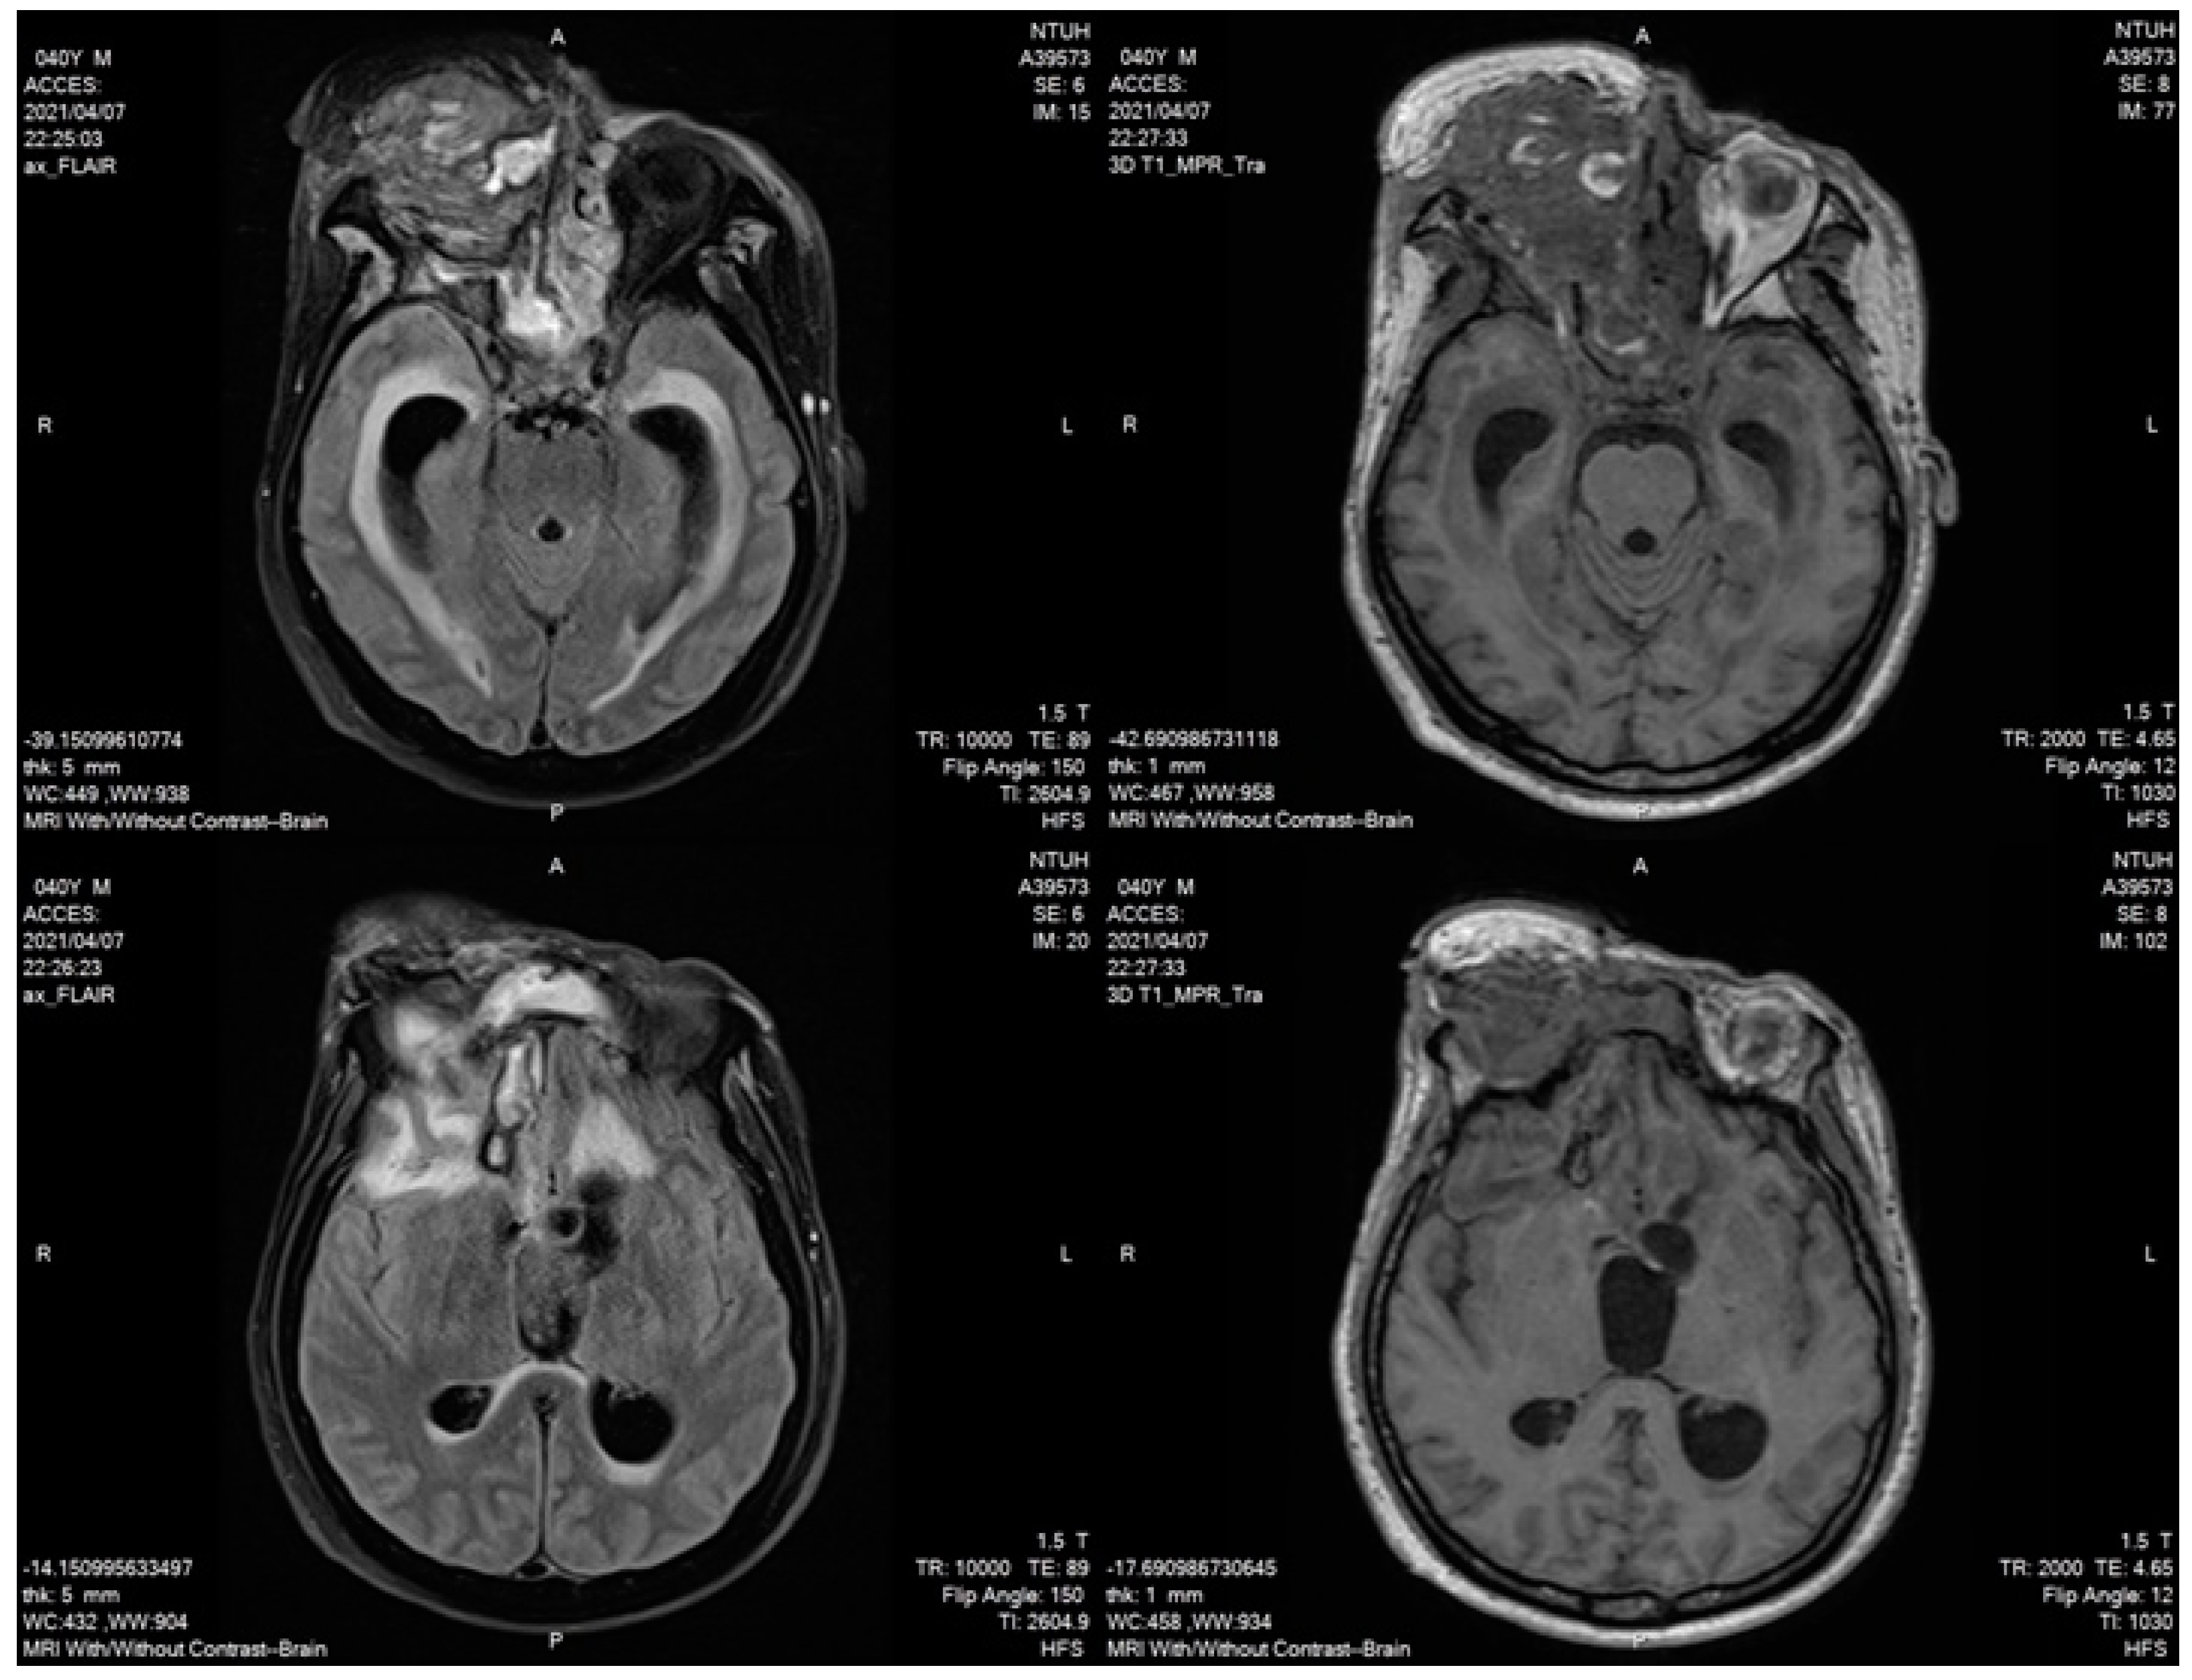

2. Case Description